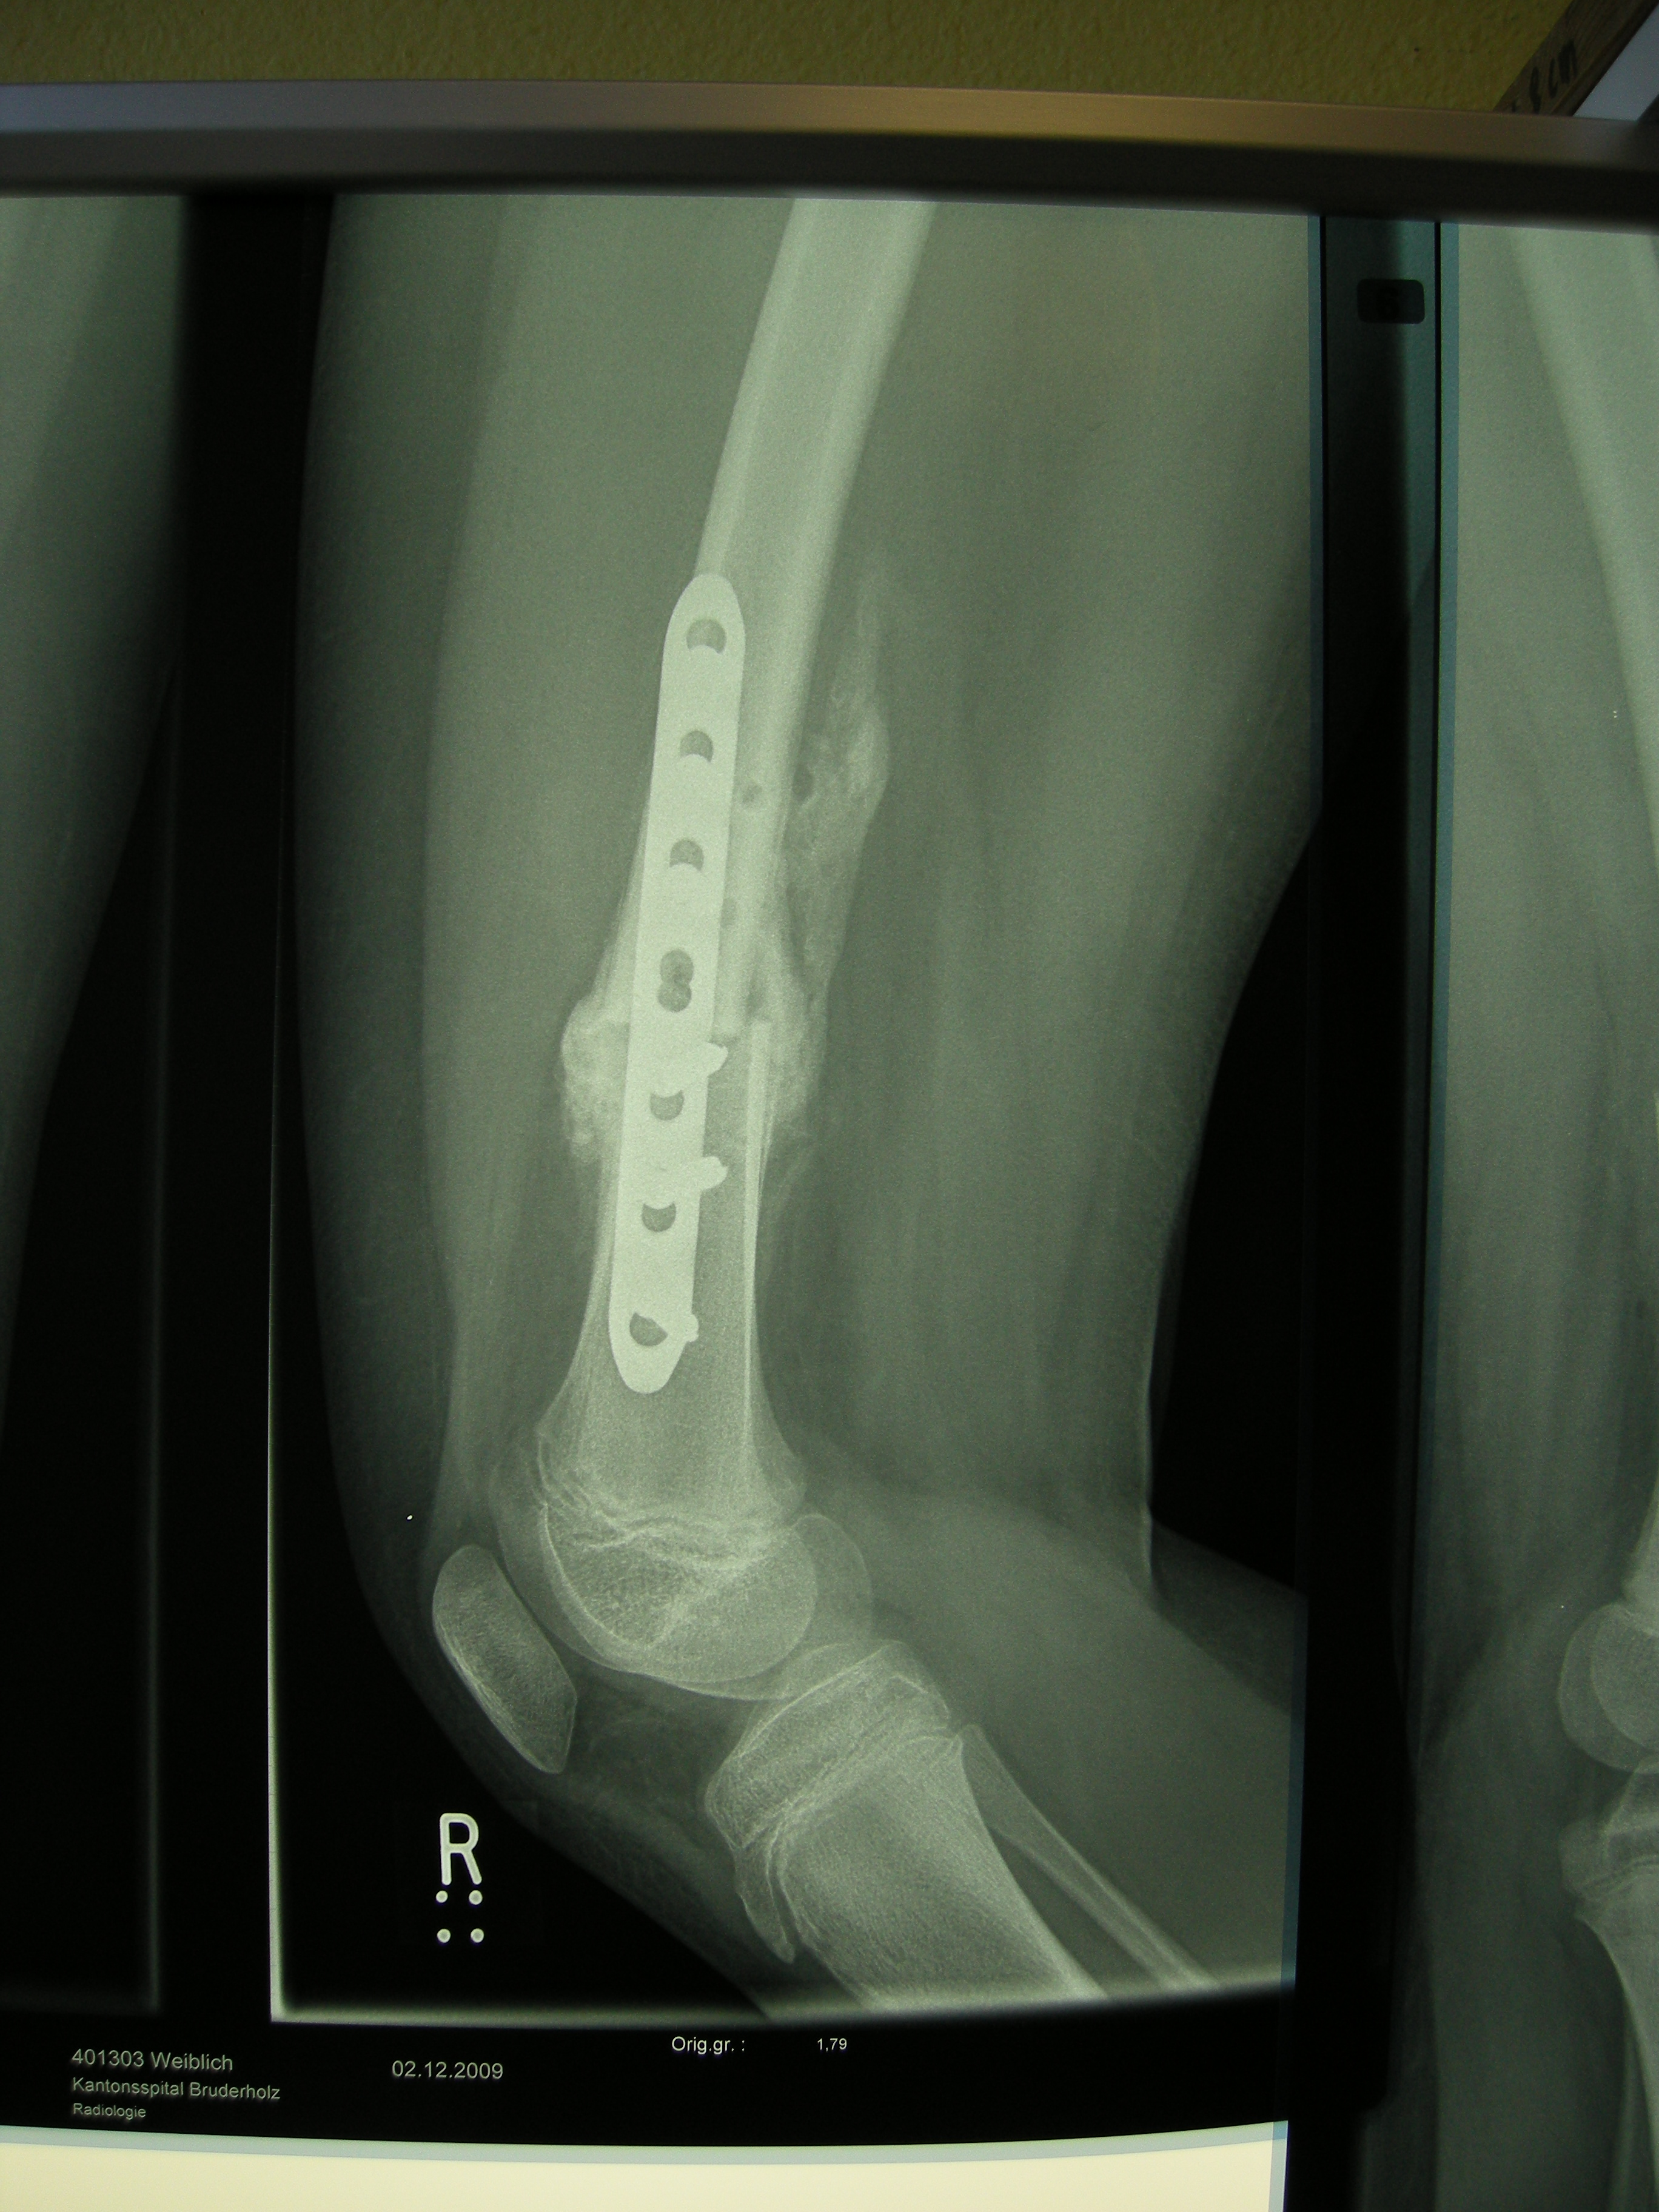

XRays